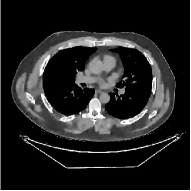

This section compares the reconstruction quality and runtime among the proposed MBIR method, PWLS-ST-, and other three MBIR methods, PWLS-EP, PWLS-DL, and PWLS-ST-. Table I shows that, for both 2D and 3D sparse-view CT reconstructions of the XCAT phantom, the proposed PWLS-ST- model outperforms PWLS-EP and PWLS-ST- in terms of RMSE. In addition, PWLS-ST- using a square transform (of size ) achieves lower RMSE than PWLS-DL using an overcomplete dictionary (of size ) for 2D sparse-view reconstructions. Fig. 3(a) and Fig. 4 show the reconstructed images for 2D and 3D phantom experiments, with different reconstruction models and different number of views. (See the corresponding error maps in the supplement.) The proposed PWLS-ST- consistently gives more accurate image reconstructions compared to other MBIR methods. Specifically, PWLS-ST- has smaller errors in the heart region (see zoom-ins in Fig. 3(a)) of 2D reconstructions than PWLS-DL and PWLS-ST-. In addition, compared to PWLS-ST-, PWLS-DL and PWLS-ST- have some ringing artifacts around the edges with high transition, e.g., edges between air and soft tissues. (See a comparison of profiles of PWLS-ST- and PWLS-ST- in the supplement.) In particular, PWLS-ST- and PWLS-DL give more visible ringing artifacts for 2D reconstruction from fewer views, and PWLS-ST- has these ringing artifacts for 3D reconstructions regardless of the number of views (see zoom-ins in Fig. 4). Table II reports runtimes of different MBIR methods in reconstructing the -views XCAT phantom scan. (FBPConvNet is a non-MBIR method and its runtime for processing a image is approximately one second with a TITAN Xp GPU.) While providing better reconstruction quality, the proposed Algorithm 1 of PWLS-ST- has shorter runtime compared to the algorithms of PWLS-DL and PWLS-ST- in Section III-A. Similar to the PWLS-EP algorithm, the reconstruction time of the PWLS-DL, PWLS-ST-, and PWLS-ST- algorithms can be further reduced by using ordered subsets [51].

Fig. 3(b) shows that when tested on the clinical scan data, the proposed PWLS-ST- method improves reconstruction quality in terms of noise and artifacts removal (e.g., see zoom-ins for soft-issue regions), and edge preservation (e.g., see zoom-ins for bone regions), compared to PWLS-EP and PWLS-ST-. Compared to PWLS-DL, PWLS-ST- achieves comparable image quality, but requires less computational complexity.

| (a) 2D fan-beam CT experiments |

III-B3 Generalization Capability Comparisons between a “Denoising” Deep NN and the Proposed PWLS-ST- Method

This section compares the generalization capabilities between the proposed MBIR method, PWLS-ST-, and a denoising deep NN, FBPConvNet [14], that are trained from the phantom data; in particular, we tested the trained PWLS-ST- and FBPConvNet models to phantom and clinical scan data. The results in Fig. 6 show that the non-MBIR FBPConvNet method has higher overfitting risks, compared to the proposed PWLS-ST- MBIR method. When tested on clinical scan data, PWLS-ST- achieves much more accurate reconstruction, compared to FBPConvNet. See Fig. 6(b). When tested on phantom data, FBPConvNet generates more unnatural features as the number of views reduces, although it gives lower RMSE values compared to PWLS-ST-. See zoom-ins in Fig. 6(a). The FBPConvNet results above correspond to those in the recent work [16] that FBPConvNet [14] generated some unexpected structures.